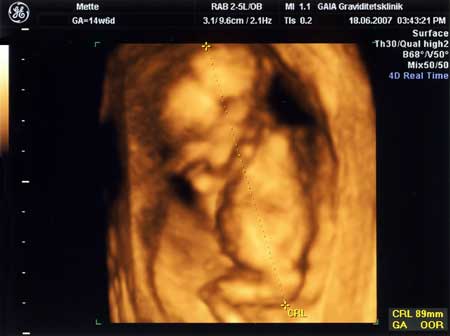

3D scanning – se baby i maven under graviditeten

3d scanning uge 14

3d scanning – uge 14

uge 14+6